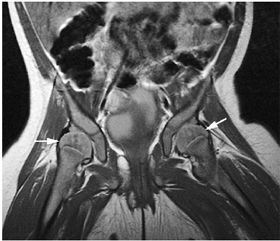

FIGURE 13.18 ● In chronic myelogenous leu-kemia, diffuse marrow involvement infiltrates regions of previous red marrow stores in the femurs (curved arrows) and acetabulum (straight black arrows) and demonstrates low signal intensity on a T1-weighted image (A) and high signal intensity on a corresponding STIR image (B). The sites where yellow marrow is spared (the greater trochanter and femoral epiphysis) demonstrate high signal intensity on the T1-weighted image and low signal intensity (from the nulled fat signal) on the STIR sequence (white arrows).

|